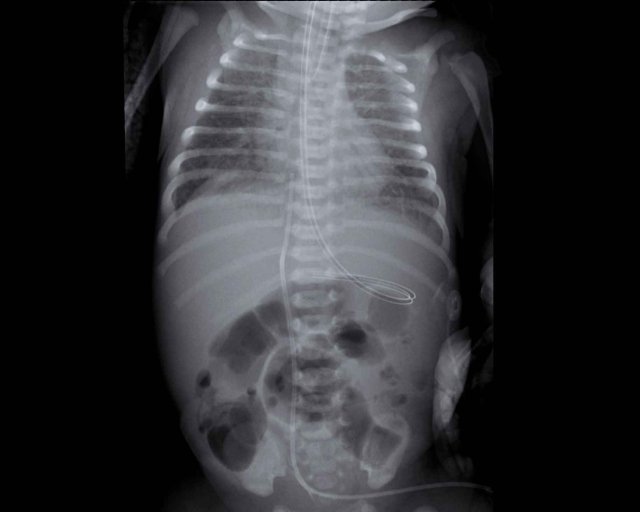

One week old neonate, born at 27 weeks of gestational age.

Image

• Deep position of the tracheal tube, which should be repositioned to the mid of the trachea.

• Diffuse granular opacification of both lungs.

• Air bronchograms.

• Pumonal vessels are not recognized anymore, but cardiac silhouette is still recognizable.

• Opacification of the left lower lobe caused by atelectasis.

No grading because this neonate is on mechanical ventilation.